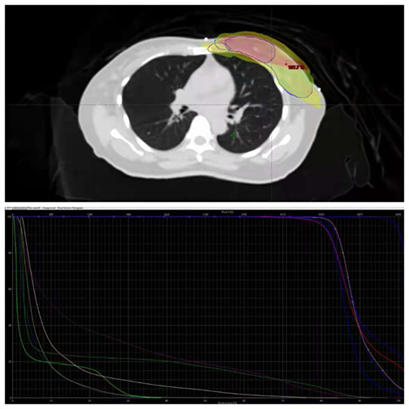

我院放疗物理师团队运用 DIBH 技术采集得到了一系列的 CT 定位扫描图像,并据此反复优化放疗方案中的照射野角度和形状,在满足靶区剂量覆盖的前提下最大限度地减少患者肺部、心脏等重要组织器官的受照剂量。放疗科医生及物理师在制定放疗方案时不仅参考了患者呼吸控制能力,尽可能地减少计划投照时间,还充分评估了放疗计划的可行性,很好地满足了临床要求,并精准完成计划验证。图像引导治疗手段是保证患者为期五周的放疗计划能被精准执行的必要条件。而 DIBH 技术的采用,使我院放疗科医生、物理与技师团队能为患者制定出高精度、高可靠性、高舒适度的图像引导治疗方案。

▲ 放射治疗计划